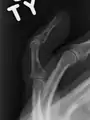

X-ray showing fracture at the insertion of the extensor tendon